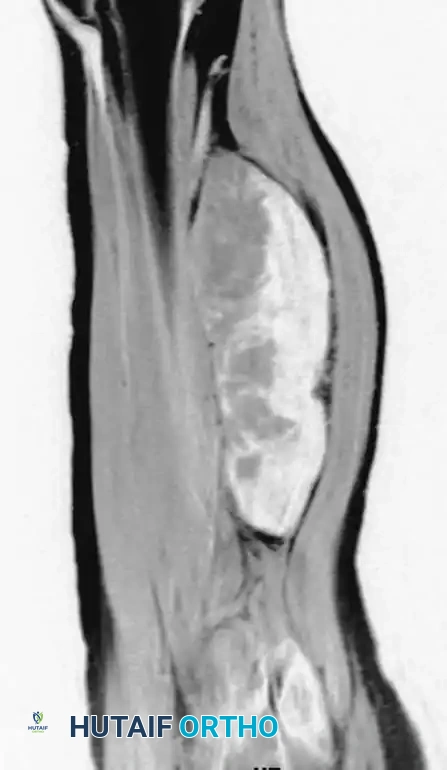

Conventional radiographs may demonstrate a non-specific soft-tissue density but are usually normal. MRI reveals a well-circumscribed mass that is typically isointense to muscle on T1-weighted images and hyperintense on T2-weighted images. Central necrosis is a hallmark of larger, high-grade tumors.

Axial MRI showing a large soft-tissue mass in the thigh with mixed signal intensity, characteristic of UPS/MFH.

Coronal MRI demonstrating the proximal-distal extent of the tumor within the muscular compartment.